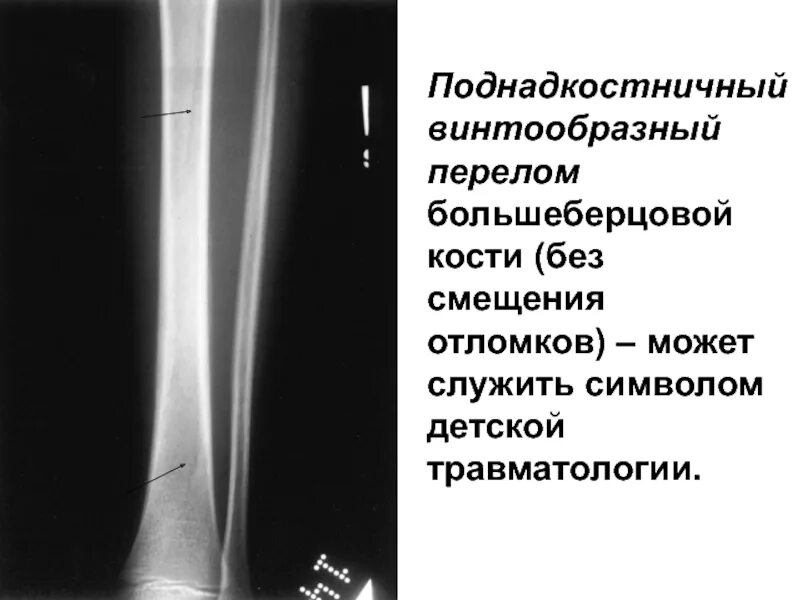

Перелом 3 берцовой кости